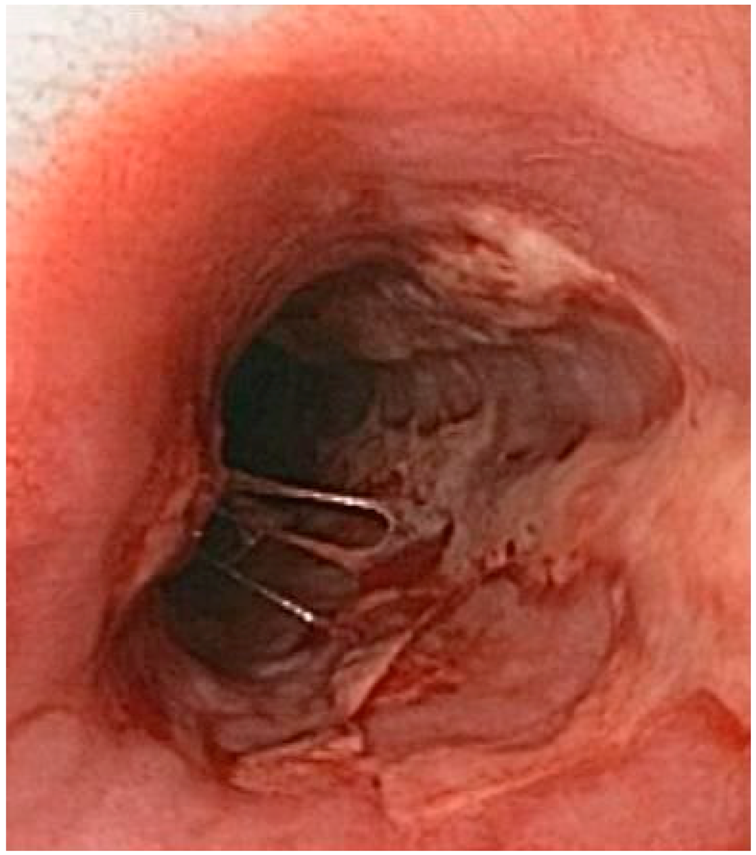

2.11.2. Disease Clinics

Following a primary infection, the virus enters the nerves at the site of primary infection, moves towards the cellular body of the neuron and becomes latent in the ganglion. As a consequence of the primary infection, the body produces antibodies for the particular type of HSV involved, preventing a subsequent infection of this type in a different site. In individuals infected with HSV-1, seroconversion after an oral infection prevents further HSV-1 infections, such as the genital herpes, or herpes of the eye. HSV-1 seroconversion also appears to reduce the symptoms of subsequent HSV-2 infection, although HSV-2 may still be contracted. Many people infected with HSV-2 show no physical symptoms; these are called “asymptomatic”, or suffering from subclinical herpes. Herpes labialis is easily identified by a simple clinical examination of individuals with no previous history of lesions and who have had contact with an individual known to be HSV-1 positive. In these subjects, in general the vesicles are multiple, of round and superficial aspect, accompanied by an acute gingivitis. Adults with atypical presentation are more difficult to diagnose. The prodromal symptoms that occur before the appearance of herpetic lesions help to differentiate the symptoms of HSV from similar symptoms of other disorders, such as allergic stomatitis. When the lesions do not appear inside the mouth, primary oral-gold herpes are sometimes mistaken for impetigo, a bacterial infection. Even common mouth ulcers (aphthous ulcers) resemble intraoral herpes but do not present a vesicular phase.